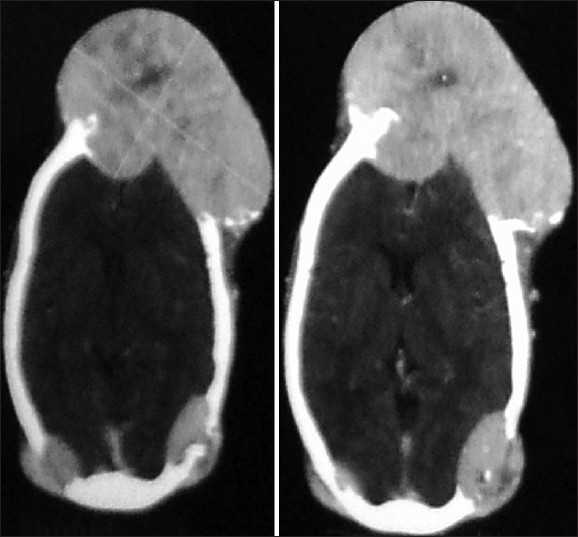

A 48-year-old female presented with swelling in the frontal region of the skull since 2 years and another swelling in parieto-occipital region since 4 months. Both the swellings over skull have been painless and gradually progressive in size, thus the delay in presentation. No significant past medical history. On examination, swelling in frontal region measured 18 cm in sagital and 13 cm in coronal directions and 7 cm in vertical dimension. The veins over swelling were distended and it was pulsatile in nature, firm in consistency and fixed to skull. The skin over the swelling was stretched but otherwise normal. Left orbit appeared distorted by the swelling but vision was normal [Figure 1]. The second swelling was located in parieto-occipital region right side and measured 3×4 cm pulsatile in nature and firm in consistency [Figure 2]. Incidentally a thyroid swelling was noted involving mainly right lobe around 3×2 cm, firm and not associated with any pressure symptoms [Figure 1]. Patient did not have any neurological deficit or psychological illness. The patient was clinically euthyroid with normal general physical, systemic, and neurological examination. Routine blood tests and thyroid function tests were normal. Ultrasound study of neck revealed 2 × 1.5 cm neoplastic solid nodule in right lobe of thyroid. Rest of the thyroid gland and neck was normal. X-ray of skull showed lytic lesion in frontal and occipital region of skull. Contrast enhanced computed tomography (CT) demonstrated a 13 × 18 cm size expansile osteolytic lesion in the fronto-parietal region on both right and left side of anterior half of skull. The lesion was extending intracranialy and causing compression of the underlying fronto-parietal lobes on both sides. Similar expansile osteolytic lesion of smaller size are seen in the occipital region on both sides largest measuring 4×3 cm on right side. On postcontrast study, these lesions showed significant enhancement suggesting increased vascularity and also areas of necrosis were present at centre [Figure 3]. Fine needle aspiration cytology (FNAC) from thyroid nodule was reported as follicular neoplasm. FNAC from skull swelling obtained was stained with Leishman stain. Smears showed many syncytial sheets of thyroid follicular cells having monotonous enlarged, hyper chromatic nuclei, and microfollicles containing colloid [Figure 4]. Patient was advised total thyroidectomy and radioiodine therapy but was not willing, hence was administered supraphysiological dose of thyroxine. Till date the patient is on follow-up and able to carry out her routine activities. | Figure 1: A 13 × 18 cm metastasis follicular thyroid carcinoma in frontal region of skull swelling with distended and engorged veins suggesting increased vascularity and also showing incidentally noted 3 × 2 cm thyroid swelling the primary lesion involving right lobe of thyroid

| Figure 3: CT scan showing multiple osteolytic lesions with contrast enhancement and central necrosis